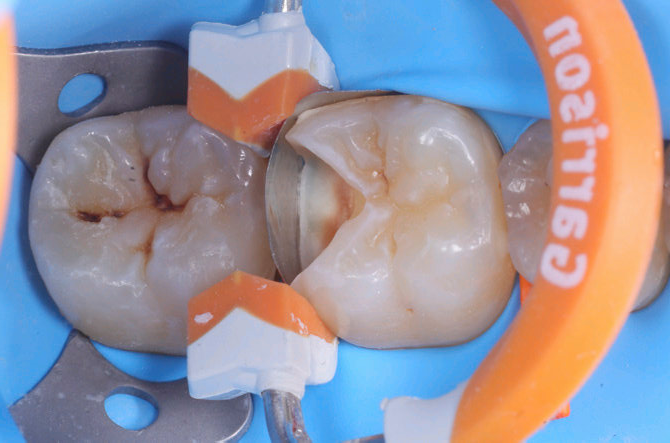

Dopo anestesia ed isolamento con diga di gomma si procede alla rimozione del tessuto cariato eseguito con frese multi-lama di grossa dimensione. Una volta completata la detersione della dentina si procede alla rifinitura dei margini in smalto con frese a granulometria ridotta e di forma appropriata.

Considerata la grossa dimensione della cavità e la vicinanza con il cornetto pulpare si opta per un sistema adesivo self etch che prevede però la mordenzatura dello smalto. Questa procedura è attuata con matrice cuneo ed anello delle corrette misure precedentemente posizionati.

Si verificano quindi i quattro punti per il posizionamento di una corretta matrice: 1. chiusura del gradino cervicale, 2. chiusura delle pareti assiali, 3. adagiamento della patrice contro il dente adiacente, 4. nessuna deformazione interna della matrice.

| Fig.1 Fotografia iniziale che evidenzia la dimensione della lesione distale | Fig.2 Aspetto della cavità ultimata sotto la diga di gomma |

| Fig.3 Posizionamento della matrice,del cuneo e dell’anello | Fig.4 Aspetto vestibolare della creazione della parete inter-prossimale |